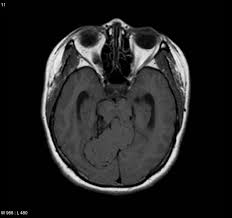

Emergency Quiz Cases

Emergency Quiz Cases from image.slidesharecdn.com